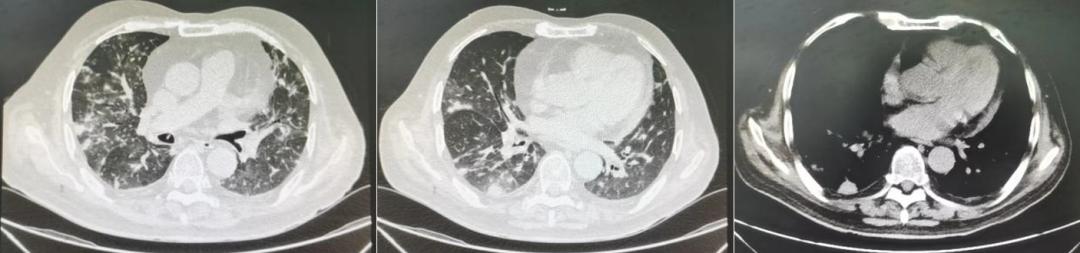

鉴于患者血象、CRP、PCT指标正常,且抗细菌治疗满1周,故予停药,继续予SMZ联合伏立康唑抗感染。然而,8月15日复查胸部CT平扫(图4)可见双肺渗出病灶较前有所缓解,但右肺新发多处结节影,性质不明。且因患者出现视力模糊,不除外伏立康唑所致神经精神异常不良反应,故改伏立康唑为卡泊芬净针50mg 1/日(首剂70mg)抗真菌治疗。

图4:2022年8月15日患者的胸部CT平扫

8月22日复查胸部CT平扫(图6),见双肺磨玻璃病灶较前明显吸收,双肺结节较前有所吸收,评估治疗有效。患者目前一般情况较前明显好转,气急症状较前明显减轻。

图6:2022年8月22日患者的胸部CT平扫